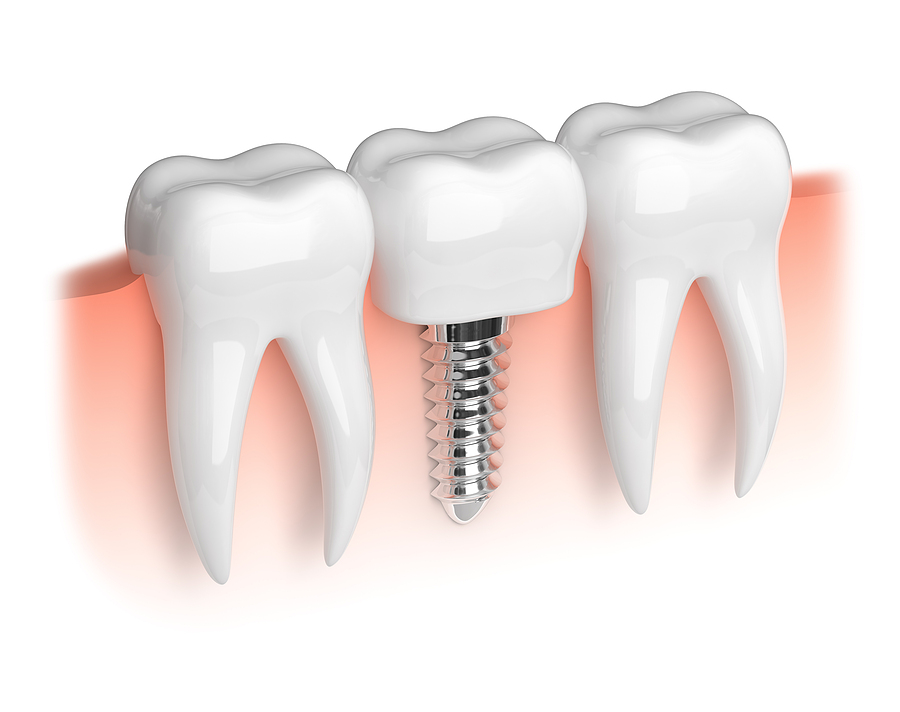

How Dental Implants Help Prevent Bone Loss and Preserve Facial Structure

Are you concerned about the impact of tooth loss on your smile? You're not alone. Many people experience anxiety when it comes to the aesthetics and health of their teeth. Missing a tooth can lead to more than just gaps in your grin; it can also trigger bone loss in the jaw, affecting your overall […]

Restoring Smiles with Precision: Exploring Implant Dentistry in Memphis, TN

Tooth loss can affect your ability to eat, speak, and smile confidently. Fortunately, advancements in dental technology offer a transformative solution: dental implants. Implant Dentistry in Memphis, TN, is revolutionizing how missing teeth are restored, providing patients with durable, natural-looking replacements that enhance function and aesthetics. If you’re considering dental implants, understanding the process, benefits, […]